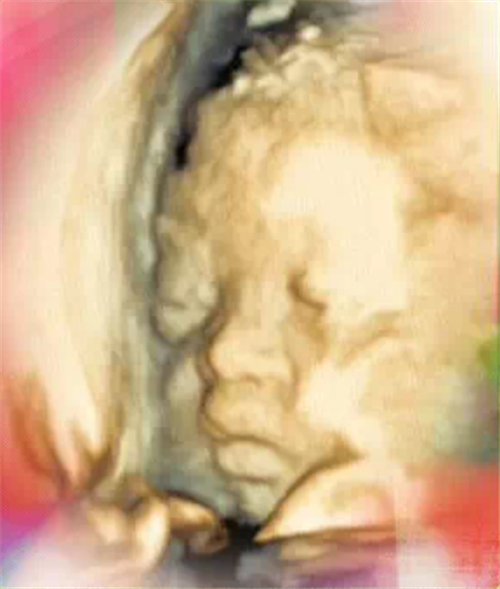

石家庄平安医院以致敬劳动者为主题,在2020年这个不同寻常的“五一”国际劳动节节日里特别推出产科三维、四维彩超八折钜惠活动,重要的是,这样的优惠不仅“五一小长假”可以享受,直至2020年年末,天天都是八折!

平安医院飞利浦EPIQ5高端智能超声诊断系统具有如下显著优势:

1、PureWave纯净波适用于困难患者成像的先进探头技术,提高声束穿透力的同时,获取了更高的图像分辨率。

2、nSIGHT成像平台是突破传统的高端超声成像平台,克服了传统架构的局限性,nSIGHT成像在整个场深度内构建近乎完美的发射波束,实现了无与伦比的性能水平。

3、解剖智能将影像变成答案,由于具有高级器官建模(采用xMATRIX 技术)和经证实的资格,便于进行检查,更具可复制性,并且提供新水平的临床信息。

4、MicroCPA 实现微小血管的显示,提升评估器官和占位内的血流灌注能力,提高诊断准确性。